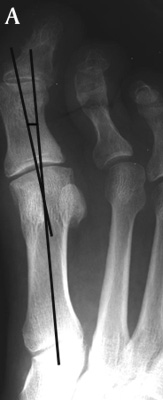

subjects HAV is 5º to 15º . Hallux abducto valgus is mild when HAV is 16º to

25º, C. moderate when HAV is 26º to 35º, and severe (D) when HAV is greater than